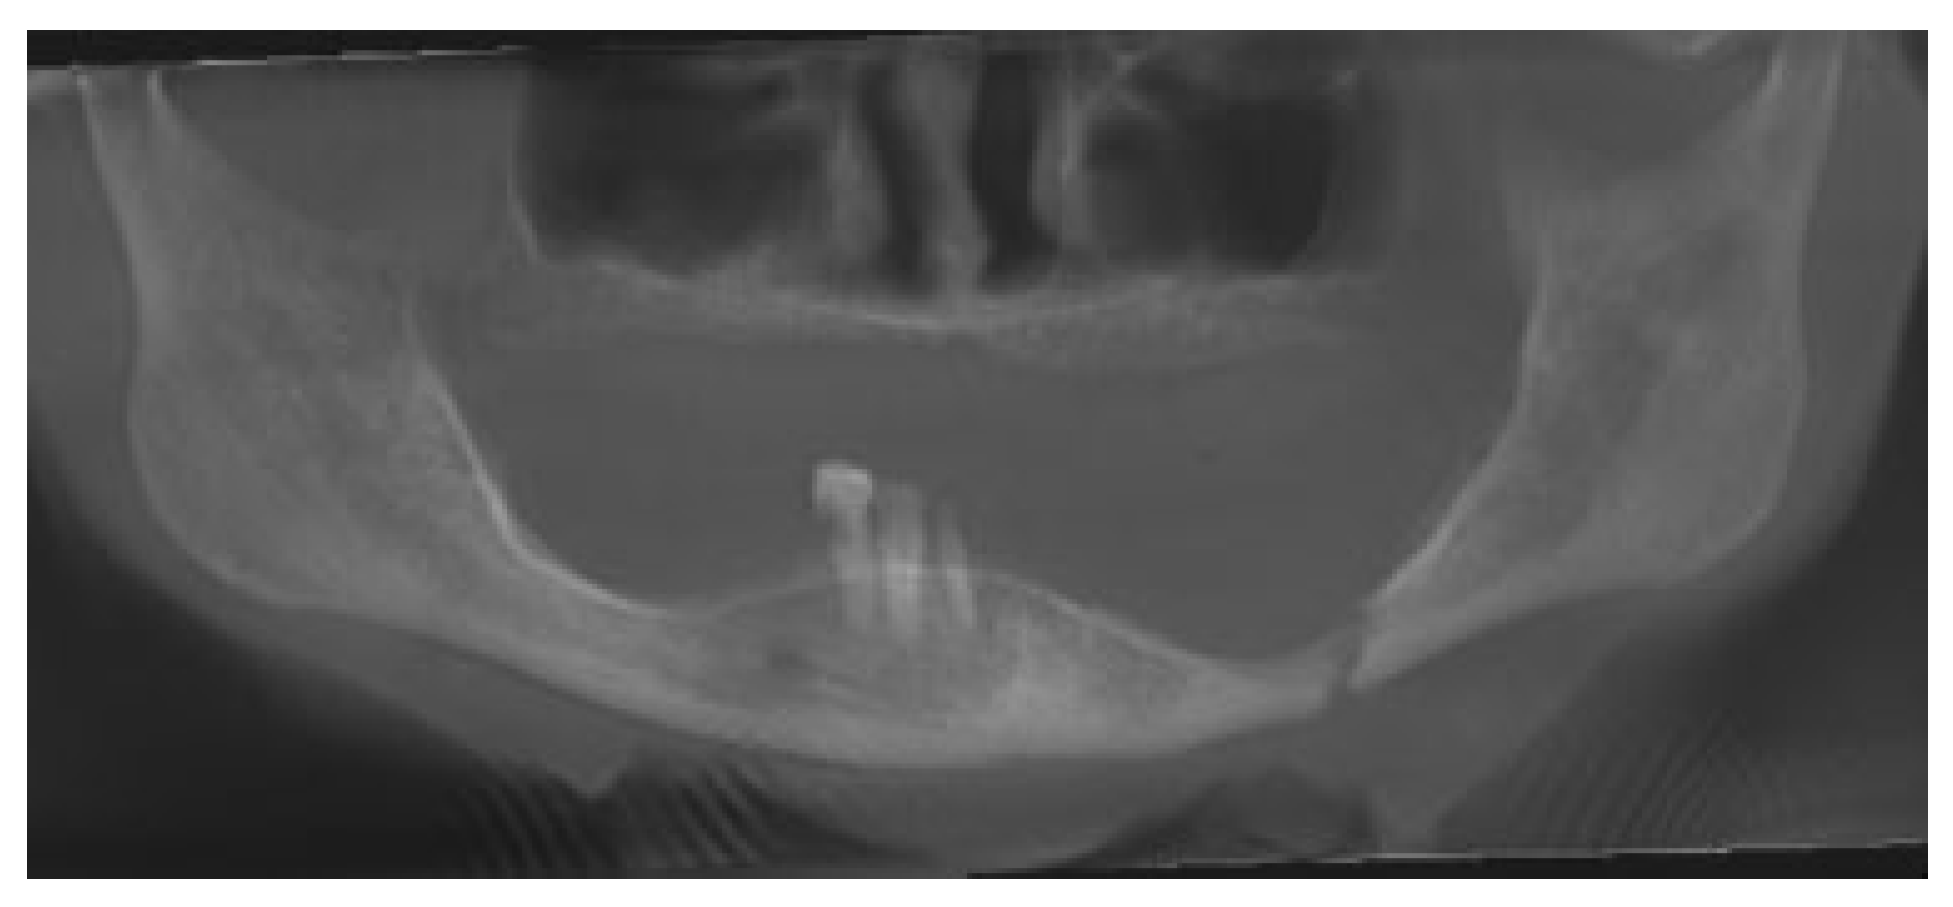

An 81-year-old woman had a fall and was diagnosed with a nondisplaced left mandible fracture. She was unsuccessfully treated with a soft diet by another oral and maxillofacial surgeon and upon repeat imaging had displacement of her fracture. She was then referred to the authors for management of her injury. Her past medical history was significant for systemiclupus erythematosus (SLE), nephritis, and a right lung mass, for which she refused workup. A CBCT was taken which showed a displaced fracture of the left mandibular body (Figure 8). VSP was again arranged using PRO PLAN. The fracture was virtually reduced and a patient-specific 2.0 mm reconstruction plate was fabricated (Figure 9, Figure 10 and Figure 11). The patient was taken to operating room and a submandibular approach was used for exposure of the left mandible. The reconstruction plate was applied after reduction and debridement of the fracture site and secured with bicortical locking screws (Figure 12). The incision was closed in layered fashion. The patient was discharged home the same day. A postoperative panoramic radiograph showed adequate reduction of the fracture (Figure 13). She went on to heal well without complication and was last seen at 6 months postsurgery.

Figure 13. Postoperative cone beam computed tomography reconstruction showing good adaptation of hardware and fracture reduction.